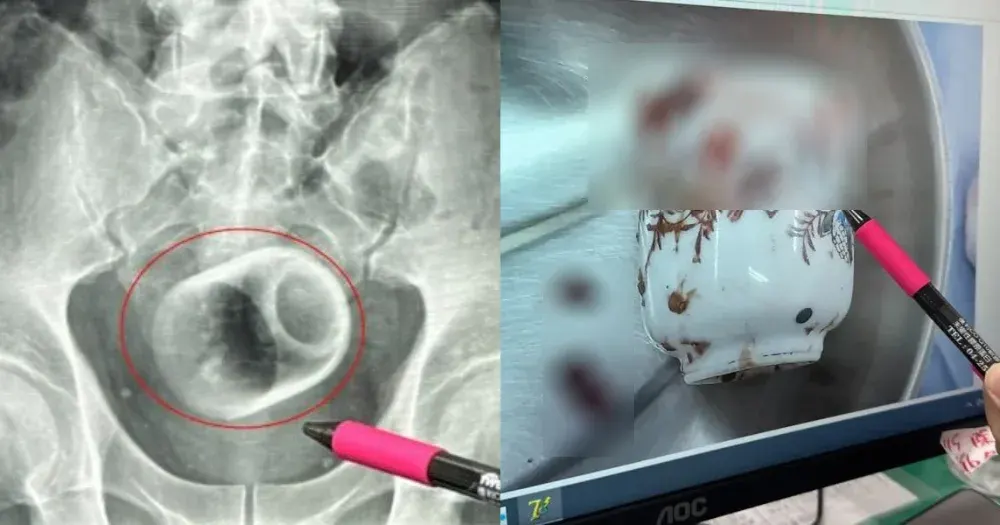

แพทย์อึ้ง!! หลังเอ็กซเรย์คนไข้ ดันพบถ้วยกาแฟในรูก้น

ชายคนหนึ่งในประเทศไต้หวัน ได้เดินทางไปพบแพทย์ หลังจากที่เขามีอาการท้องอึด ติดต่อกัน 3 วันแล้ว อีกทั้งยังทำให้เขาไม่สามารถถ่ายอุจจาระได้ ส่งผลทำให้เขาเกิดความเจ็บปวดอย่างรุนแรง...

ซึ่งแพทย์ได้ทำการเอ็กซเรย์พบว่า "มีถ้วยเซรามิกขนาดสูง 8 ซม. และ กว้าง 6 ซม. อยู่ภายในรูทวารหนักของเขา"

ถึงแม้ว่าทีมแพทย์ จะพยายามนำถ้วยออกทางช่องทวารหนัก โดยการใช้เครื่องมือหลายชนิด รวมถึงกล้องส่องเพื่อส่องผ่านผนังช่องท้อง แต่ก็ไม่สำเร็จเนื่องจากถ้วยลื่นเกินไป และ ในที่สุดชายคนดังกล่าว จำเป็นต้องเข้ารับการผ่าตัดเป็นระยะเวลานาน 2 ชั่วโมง โดยการนำถ้วยดังกล่าวออกทางลำไส้ พร้อมสร้างทวารเทียม เพื่อให้ผู้ป่วยสามารถขับถ่ายได้...

ชายคนดังกล่าว กล่าวในภายหลังว่า "ผมไม่รู้ว่าถ้วยดังกล่าว เข้ามาในรูก้นผมได้อย่างไร?"

แพทย์ของโรงพยาบาล กล่าวว่า "แม้การใส่วัตถุแปลกปลอมเข้าทวารหนัก ไม่ใช่เรื่องที่ไม่เคยเกิดขึ้น แต่สามารถก่อให้เกิดความเสียหายร้าย แรงต่ออวัยวะภายในและอาจถึงแก่ชีวิตได้!!" และ "วัตถุแปลกปลอมที่พบบ่อยได้ ได้แก่ ลูกเบสบอล เครื่องสั่น และ มะพร้าว ซึ่งอาจถูกใส่เพื่อความสนุกสนาน หรือ ความอยากรู้อยากเห็น..."